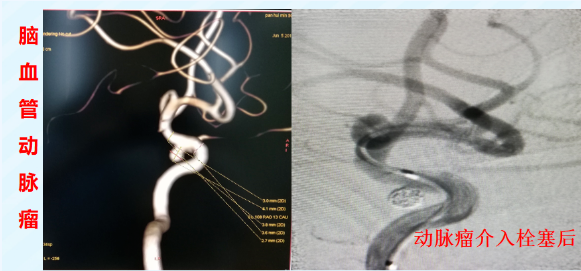

脑血管病: 急性缺血性脑卒中的动脉取栓、颈动脉或颅内动脉狭窄的支架植入以预防中风、颅内动脉瘤的弹簧圈栓塞等。